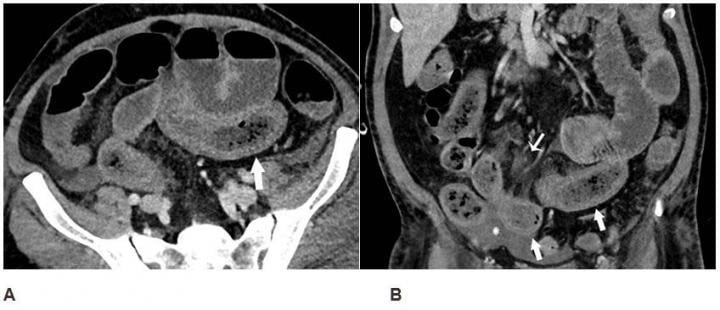

Axial (A) and coronal (B) CT of the abdomen and pelvis with IV contrast in a 57-year-old man with a high clinical suspicion for bowel ischemia. There was generalized small bowel distension and segmental thickening (arrows), with adjacent mesenteric congestion (thin arrow in B), and a small volume of ascites (* in B). Findings are nonspecific but suggestive of early ischemia or infection. Image courtesy of RSNA

Records showed that 17% of patients had cross-sectional abdominal imaging, including 44 ultrasounds, 42 computed tomography (CT) scans, and 1 magnetic resonance imaging (MRI). Bowel abnormalities were seen on 31% of CT scans (3.2% of all patients) and were more frequent in intensive care unit (ICU) patients than other inpatients. Bowel findings included thickening and findings of ischemia such as pneumatosis (gas in the bowel wall) and portal venous gas. Surgical correlation in four patients revealed unusual yellow discoloration of bowel in three of the patients, and bowel infarction (dead bowel) in two patients.

In two patients who had bowel resection, pathology demonstrated ischemia with patchy necrosis (injury due to reduced arterial flow with patchy areas of cell death). Both had fibrin thrombi (blood clots) in submucosal arterioles (small arteries in the bowel wall), suggesting bowel ischemia in these patients might be caused by these small blood clots. Lung base findings led to a diagnosis of COVID-19 in one patient who presented with abdominal symptoms only. Of right upper quadrant ultrasounds, 87% were performed for liver laboratory findings, and 54% demonstrated a dilated sludge-filled gallbladder suggestive of cholestasis, or a decrease in bile flow.

“Some findings were typical of bowel ischemia, or dying bowel, and in those who had surgery we saw small vessel clots beside areas of dead bowel,” Bhayana said. “Patients in the ICU can have bowel ischemia for other reasons, but we know COVID-19 can lead to clotting and small vessel injury, so bowel might also be affected by this.”

According to the researchers, possible explanations for the spectrum of bowel findings in patients with COVID-19 include direct viral infection, small vessel thrombosis, or nonocclusive mesenteric ischemia. “ACE2 expression is most abundant in lung alveolar epithelial cells, enterocytes of the small intestine, and vascular endothelium suggesting that small bowel and vasculature may be susceptible to SARS-CoV-2 infection,” they wrote.